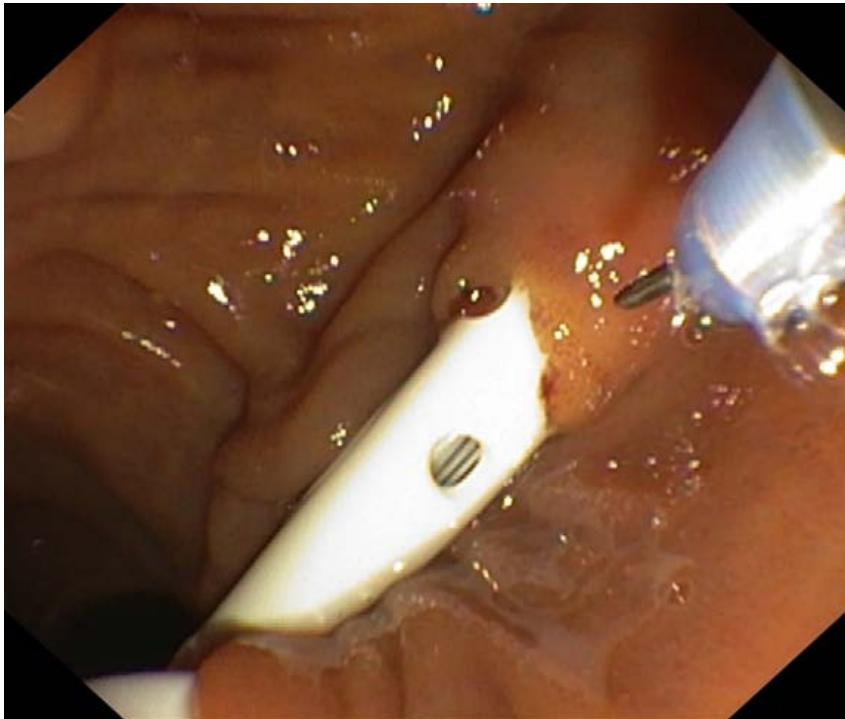

Figures 12-15 show the stages of transcholangiostomy trephine biopsy with external-internal drainage of the bile ducts and endoscopic papillsphincterotomy.

Fig.15: Endoscopic papillosphincterotomy.